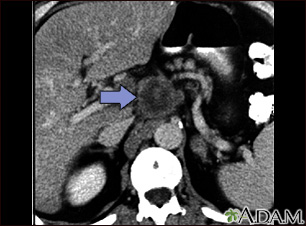

A CT scan of the upper abdomen showing a tumor (pancreas carcinoma) in the head of the pancreas, seen here in the middle of the picture.